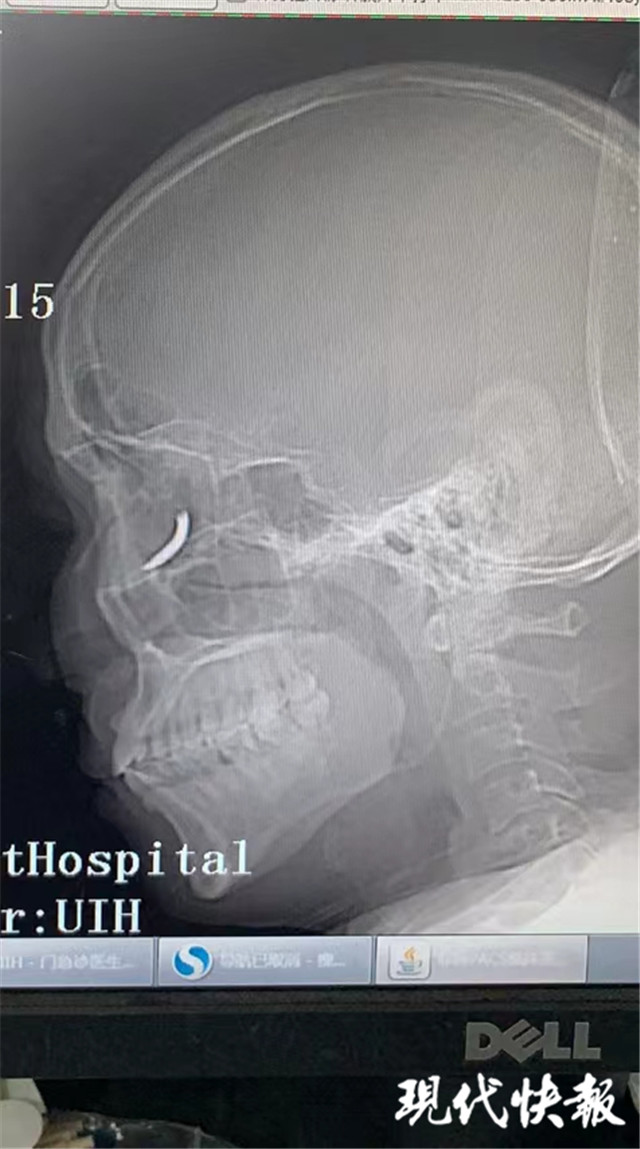

(通訊員 孫忠河 記者 梅書華)鐵釘扎入眼眶,卻不疼不癢,這是怎么回事?三天前,王師傅在溧水的建筑工地干活時,突然感覺有異物進入眼內(nèi),但沒當回事,后來出現(xiàn)頭暈才就診,沒想到是鐵釘扎入了眼眶。南京市第一醫(yī)院醫(yī)生通過半小時手術(shù),順利將一根長約一公分的鐵釘取出。

“當時在敲鐵釘,感覺什么東西進眼睛里了,但沒影響視力,還以為是水泥灰之類的。”三天前,王師傅眼中進入異物,感覺頭暈不適后,去當?shù)蒯t(yī)院就診,拍了X光片后,竟然發(fā)現(xiàn)自己眼眶內(nèi)有一個鐵釘樣的異物。

隨即,王師傅趕到南京市第一醫(yī)院眼科就診,眼科門診曹雪倩醫(yī)生接診后,立即完善CT等相關(guān)檢查。剛準備休息的眼科醫(yī)生范偉杰,立即與副主任醫(yī)師趙貴陽聯(lián)合研究這個特殊的病例。專家們發(fā)現(xiàn)這枚鐵釘不偏不倚正好扎進病人的眼眶里,但是眼眶內(nèi)解剖結(jié)構(gòu)復(fù)雜,要在盡可能保護正常組織結(jié)構(gòu)的情況下完成探查并取除鐵釘,手術(shù)難度較大。

范偉杰與趙貴陽反復(fù)討論后,制定了詳細周密的手術(shù)方案,最終以局麻下、眼袋美容切口進入,順利取出了一根長約一公分的鐵釘。整臺手術(shù)耗時半小時,手術(shù)過程中沒有損傷到眼球壁和視神經(jīng),但醫(yī)生發(fā)現(xiàn)因為鐵釘?shù)那秩?,視網(wǎng)膜周邊有出血,所以做了視網(wǎng)膜光凝。術(shù)后視力1.0,面部看不出瘢痕。王師傅的眼球終于安全保住了。